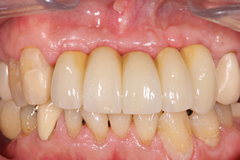

自己採血してCGF&AFGを再生に使用した症例

<治療前>

上顎前歯部が崩壊して残すことが出来ない状態になっている。

<治療後>

抜歯した部位にインプラントを埋入し半年かけて

歯肉と歯槽骨を再生させて審美的な歯(セラミック冠)を入れました。